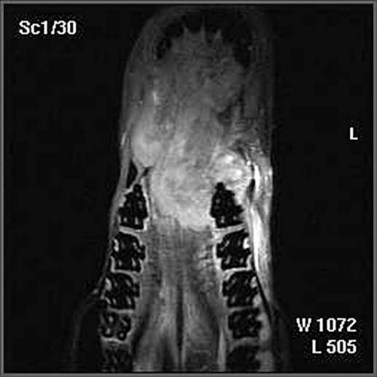

3. Magnetic resonance imaging (MRI) is an ideal modality for imaging soft tissues, and whilst the facilities for this are currently limited, they are increasing. MRI imaging suffers from the need for immobility and takes a considerable time to perform; therefore, general anesthesia is almost compulsory. Again, a three-dimensional image can be generated, and this greatly helps in dealing with soft tissue tumors and other masses within sites that preclude full inspection. The full extent of the tumor and its anatomic relationships can be revealed (Fig. 11.2).

image

Fig. 11.2 This oro-nasal palatine carcinoma was subjected to MRI scanning, and the 3-dimensional images significantly assisted the assessment of the options available to the clinician.

(Courtesy A.J. van den Belt.)